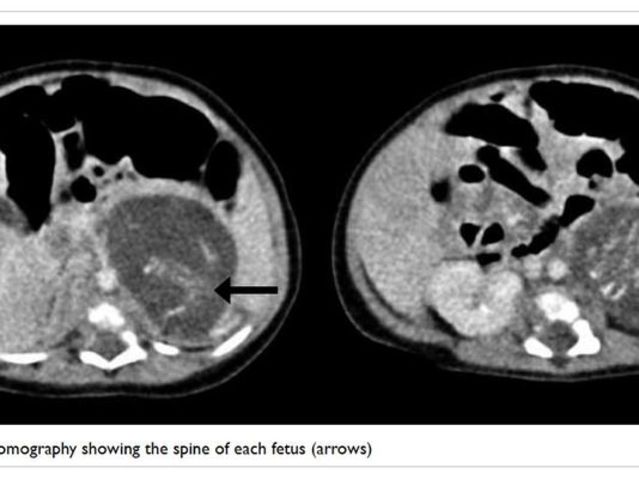

During November of 2010, it was originally thought that a young girl was born with two tumors, but now researchers have found that they were actually two very small fetuses. They were set far enough apart that they were able to develope some organs and bones. About 200 cases have been reported and it is believed that it happens in about 1 out of 500,000 births worldwide.